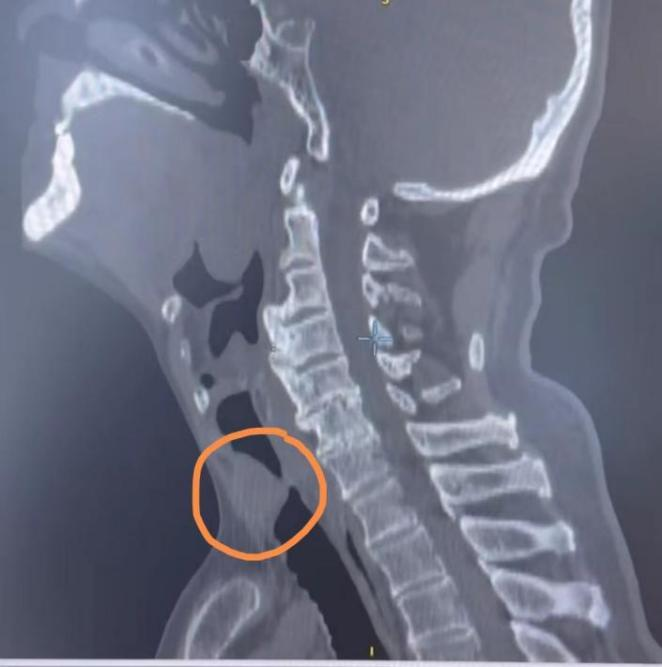

林先生,70岁,既往有恶性淋巴瘤病史已达六年,近日因“突发呼吸困难两天”送至昆山市一医院急诊室抢救,经详细检查,发现声门下缘及气管近端管口新生物生长,随时可能出现气道完全阻塞,导致窒息死亡。

这是一场与时间的赛跑,呼吸与危重症医学科李涛主任医师团队第一时间在局麻下行气管镜急诊探查,见患者声门下2CM气管内肿瘤新生物完全梗阻,管腔呈“一线天”状,他小心翼翼的在高频电下消融+圈套部分肿瘤病灶,使得患者呼吸困难显著改善,血氧饱和度回升到正常值,紧接着予以二次手术。